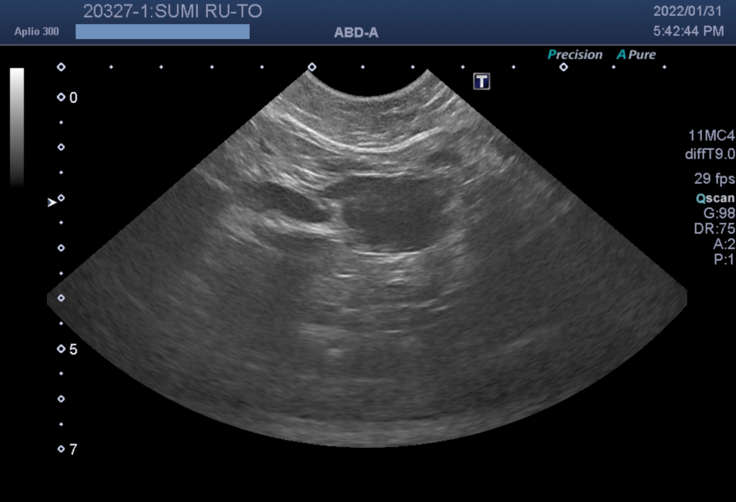

↓超音波・X線検査

リンパ

腫は血液のがんで、外科的治療(摘出)ができないので以下の選択をすることになりました。